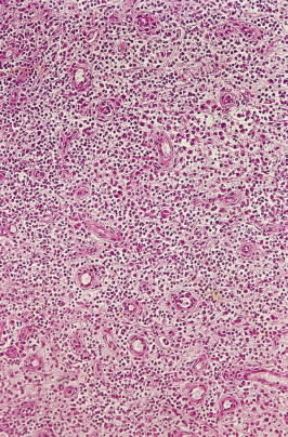

Infiammazione . Infiammazione purulenta del tessuto connettivale sottocutaneo.

De Agostini Picture Library